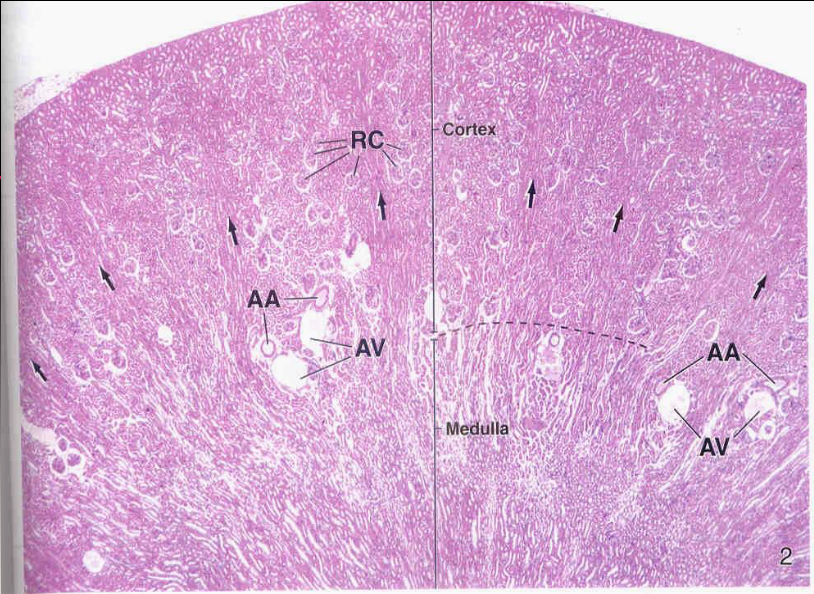

Ginjal (terdiri dari) :

• Cortex

• Medula

•Saluran Keluar urine

AA = Artery Arcuata

VA = Vena Arcuata

tanda panah = medullary rays

Cortex

Makroskopis

ØWarna gelap kecoklatan, tmpak bentukan bulat kecil (granula) Renal corpuscle & Tubulus

ØGaris-garis sejajar (Medullary Rays/ Processus- Ferreini) merupkan tonjolan tubulus